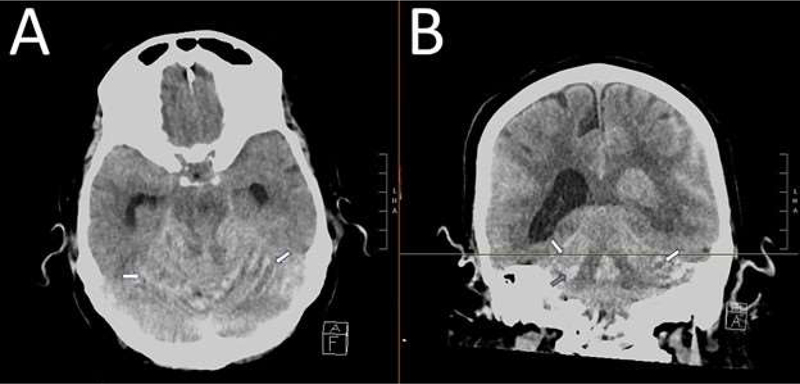

A 75-year-old woman was admitted for thoracoabdominal aneurysm repair and underwent lumbar drain placement to reduce the risk of spinal cord ischemia, initially at a rate of 10–12 cubic centimeters per hour (cc/hour). On postoperative day 1, the patient developed mild weakness of left knee flexion, presumed to be due to spinal cord ischemia. Medications were administered to raise blood pressure, and cerebrospinal fluid (CSF) drainage was increased to 15 cc/hour. The following morning, the patient experienced a severe headache, prompting a reduction in CSF drainage back to 10 cc/hour. A computed tomography (CT) scan of the head at that time did not reveal any hemorrhage, although a small pneumocephalus was present. Later that day, the patient’s headache severity increased, and she developed altered mental status, upward gaze deviation, slurred speech, and concerns for airway protection. Blood was noted in the lumbar drain. A repeat CT head scan showed interval development of an acute hemorrhage layering along the superior and lateral sides of the cerebellar folia bilaterally, localized parenchymal hemorrhage within the right inferior cerebellum, left-sided intraventricular hemorrhage, diffuse cerebral edema, and mild hydrocephalus (Figure 1).

Figure 1

Figure 1. A: Axial section of non-contrast CT head. The white arrow indicates the layering of blood in the folia of the superior cerebellum, creating a streaky pattern (Zebra sign) due to blood spreading in the cerebellar sulci. B: Coronal section of non-contrast CT head. The white reference line indicates the region of the axial section. White arrows show the layering of blood in the folia of the superior cerebellum. The grey arrow indicates a small area of cerebellar hemorrhage. Also visible are diffuse subarachnoid hemorrhage (left greater than right) and left-sided and fourth ventricle intraventricular hemorrhage.